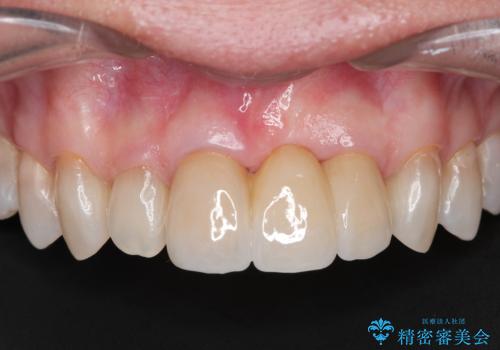

前歯の変色が気になる〈セラミッククラウン〉

担当医 瀧村怜未